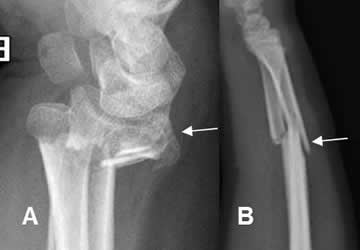

Fig 47. Fractura diastasada.

A: y B: Rx lateral. Fracturas conminutas, rotadas y diastasadas en las diáfisis femorales.